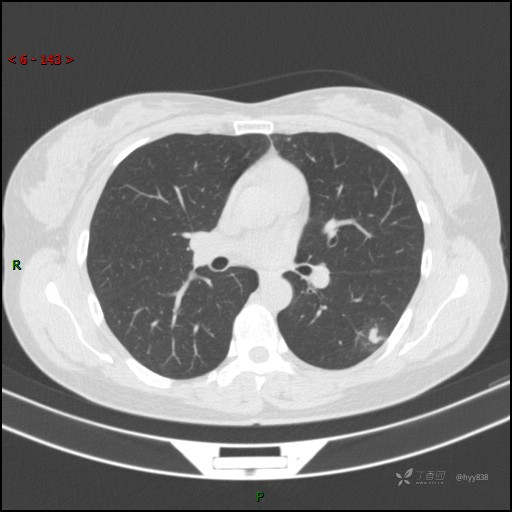

胸膜下“煎鸡蛋征”,感染 VS 炎症 VS 肿瘤,挑战有你---结果公布~

患者性别:女

患者年龄:46岁

简要病史:干咳半月伴左胸部不适

辅助检查:CT

临床诊断:结节

讨论:病变性质?